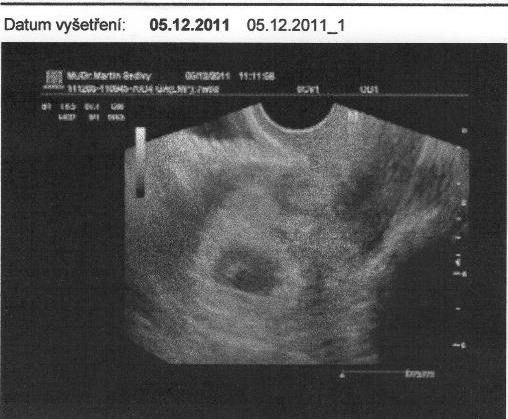

[59974] Ahojky, tak jsem byla včera na gyndě... vše je ok !!! jsme teda dneska v 8 +0 tt... to je pakárna to počítání, včera mi to vysvětlil...já počítala nějak záhadně o týden více :-) no prcek má srdíčko, krásně bušilo,....na ultrazvuku je jen flíček...ale jukněte...maličko vidět je